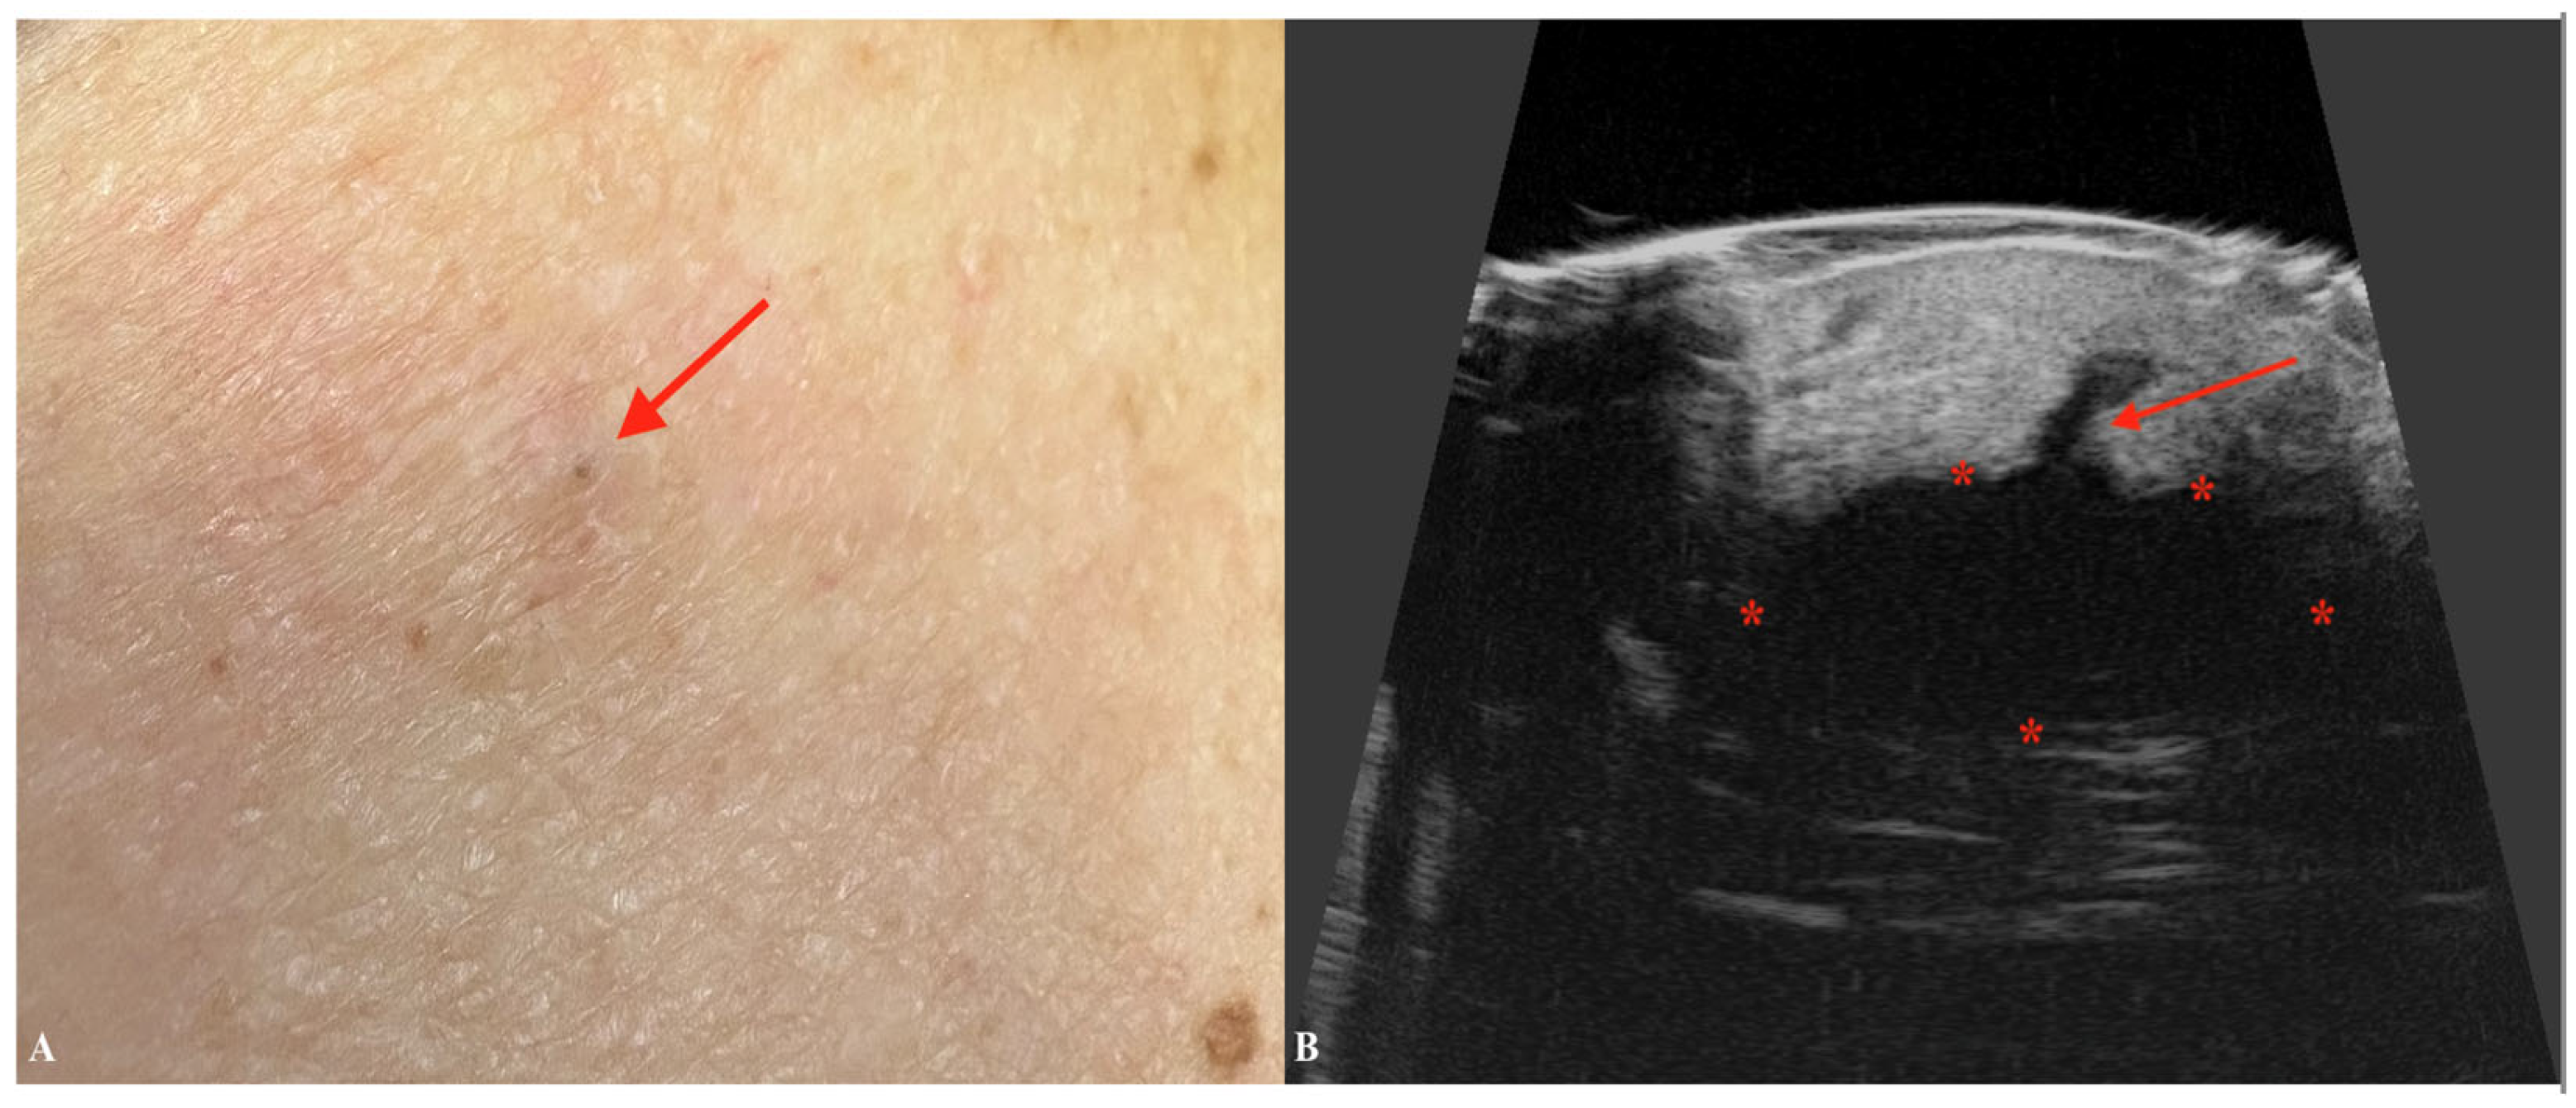

6. Mycosis Fungoides

| Mycosis Fungoides | Presence of a subepidermal low-echogenic band (SLEB). Useful in monitoring disease progression and response to therapy. |